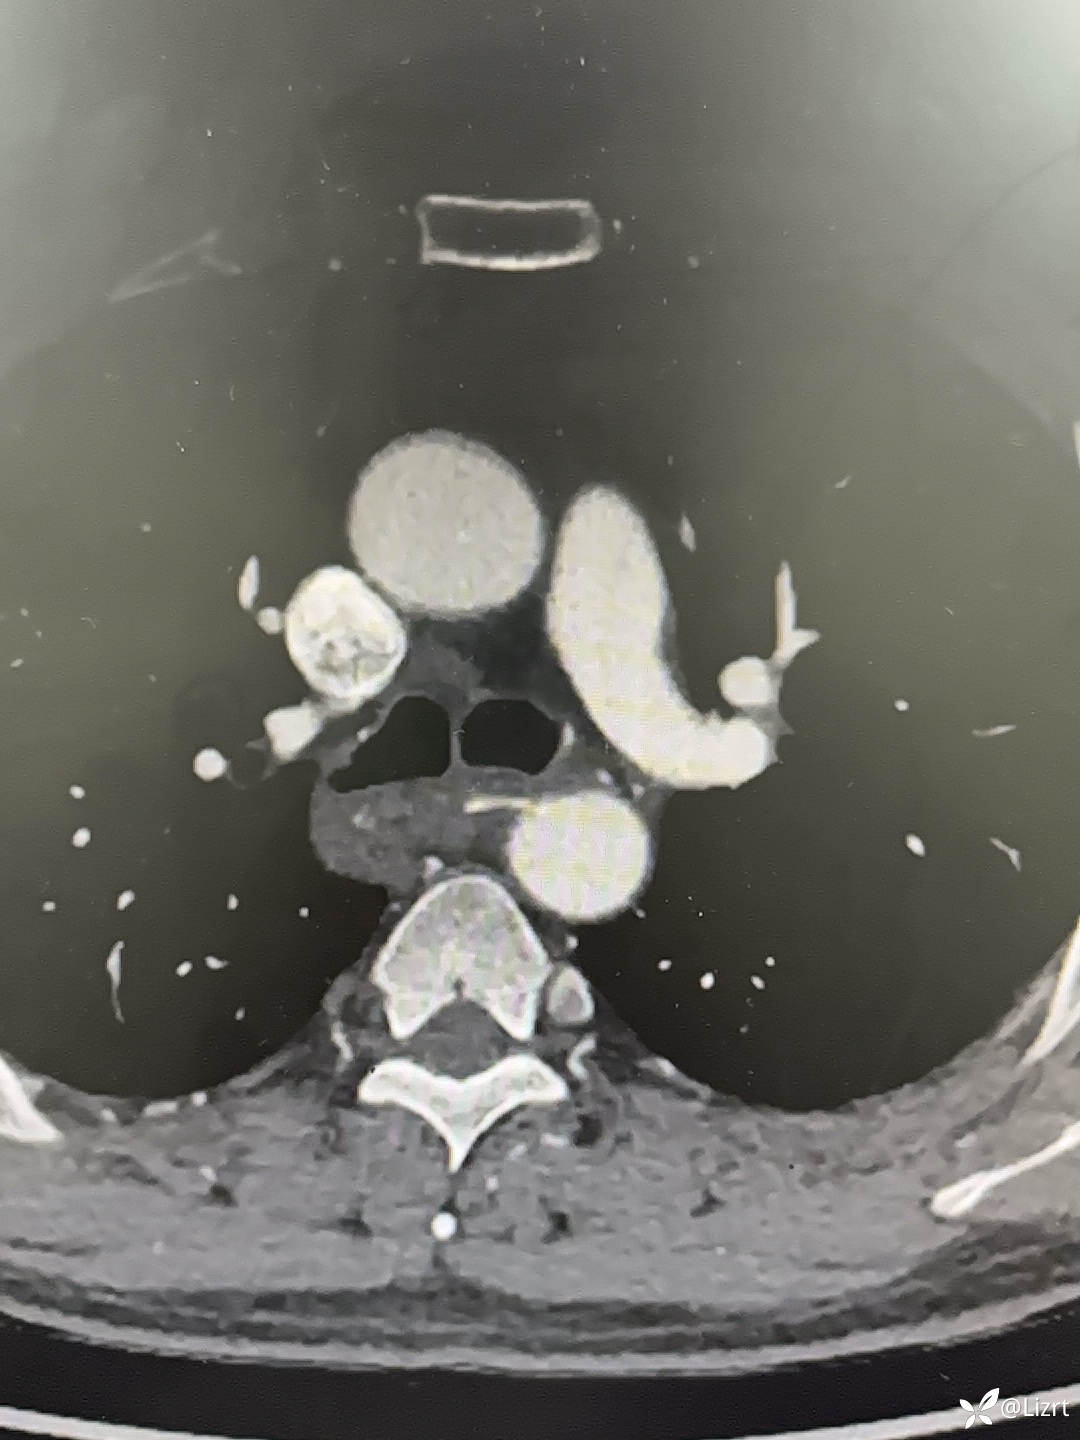

食管中段(T5水平)异物,穿透食管,刺入临近主动脉。

胸腹主动脉CTA,可见食管中段的高密度异物影,主动脉周围渗出不明显。